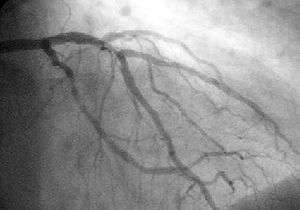

Coronary catheterization

Coronary catheterization uses pressure monitoring and blood sampling through a catheter inserted into the heart through blood vessels in the leg to determine the functioning of the heart, and, following injections of radiocontrast dye, uses X-ray fluoroscopy, typically at 30 frames per second, to visualize the position and volume of blood within the heart chambers and arteries. Coronary angiography is used to determine the patency and configuration of the coronary artery lumens.